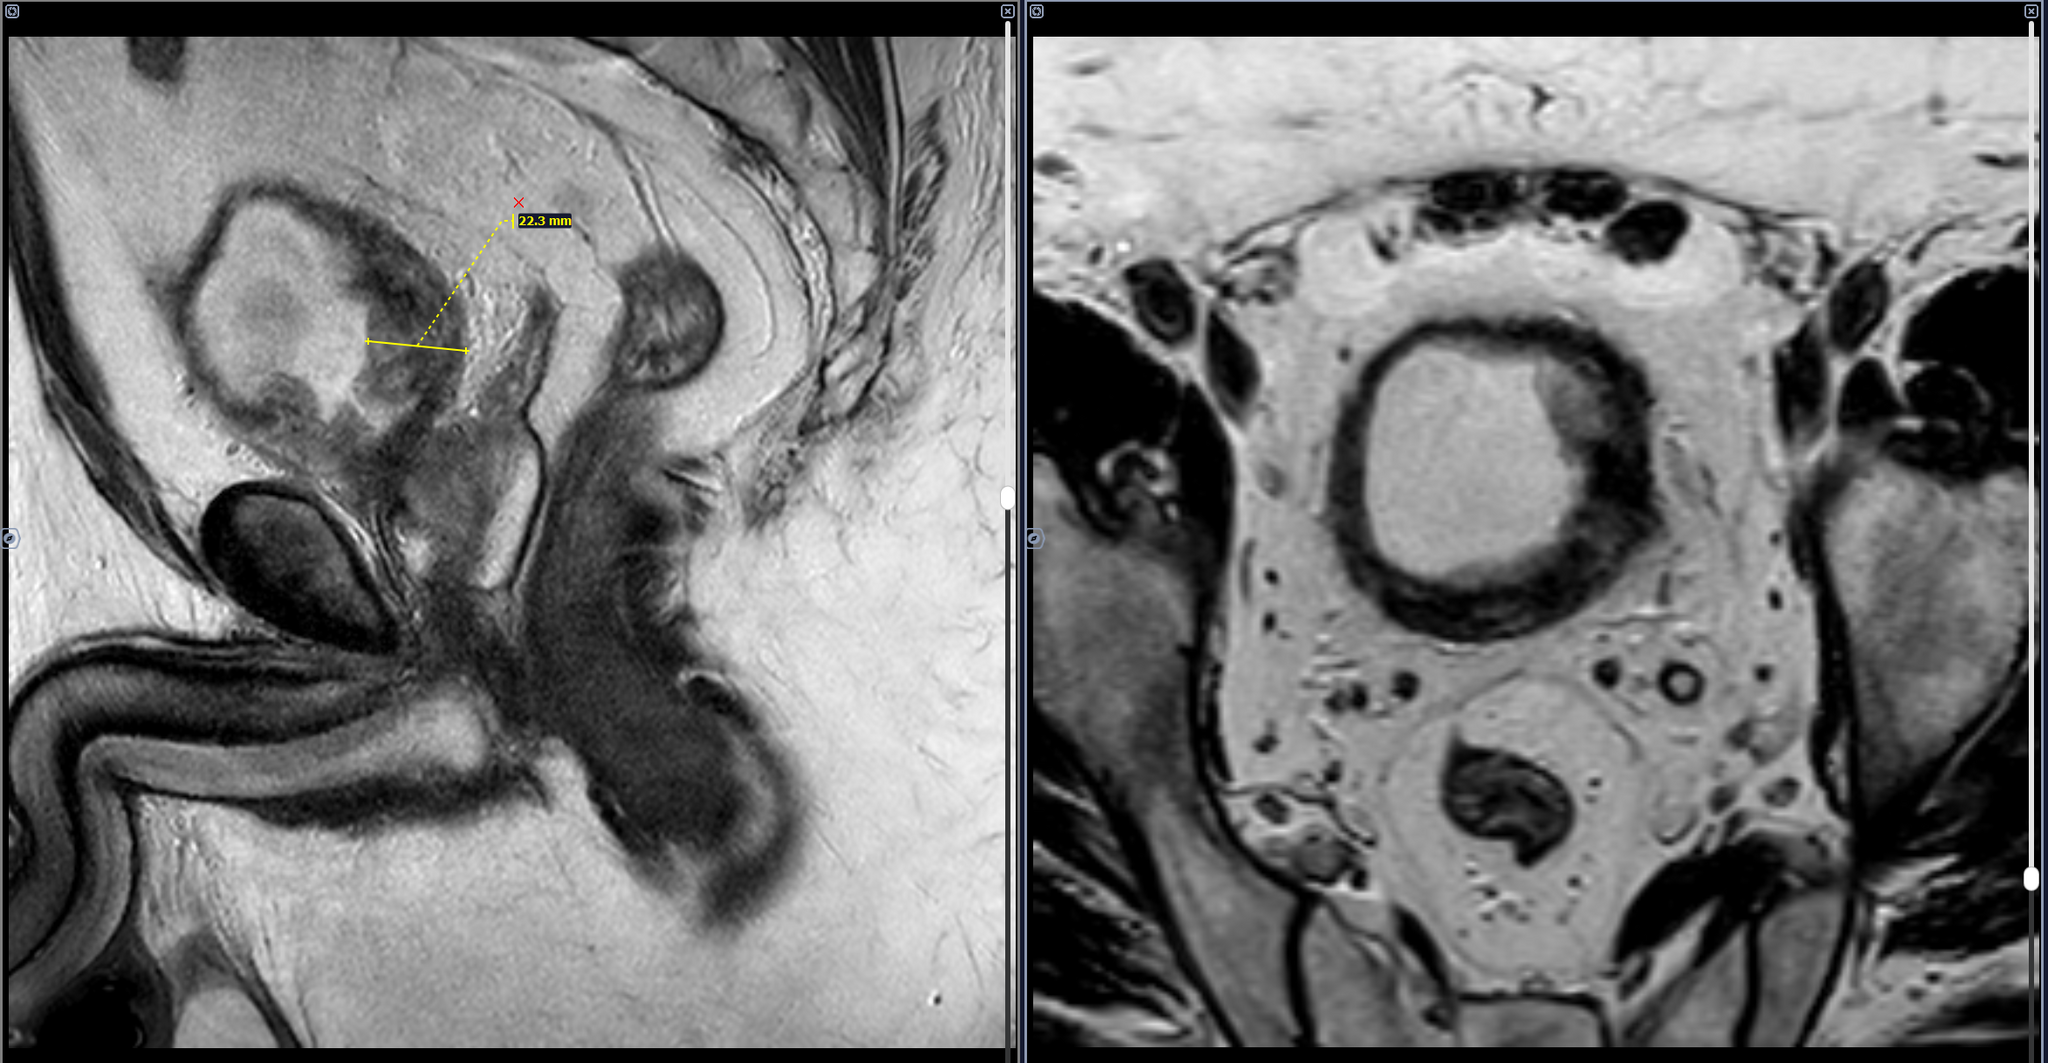

Мочевой пузырь заполнен умеренно, стенки его неравномерно утолщены, в полости визуализируется объемное солидное образования, с четкими, бугристыми контурами, исходящие: из левой боковой и частично задней стенок на 12-18 часах условного циферблата в аксиально проекции, прорастающее все стенки мочевого пузыря с микроскопической тяжистостью окружающей паравезикальной клетчатки слева, с деформацией стенок мочевого пузыря, с зонами ограничения диффузии(гиперсигнал на DWI, гипо на ИКД) во внутренних отделах образования. Предстательная железа увеличена в объеме-признак ДГПЖ.